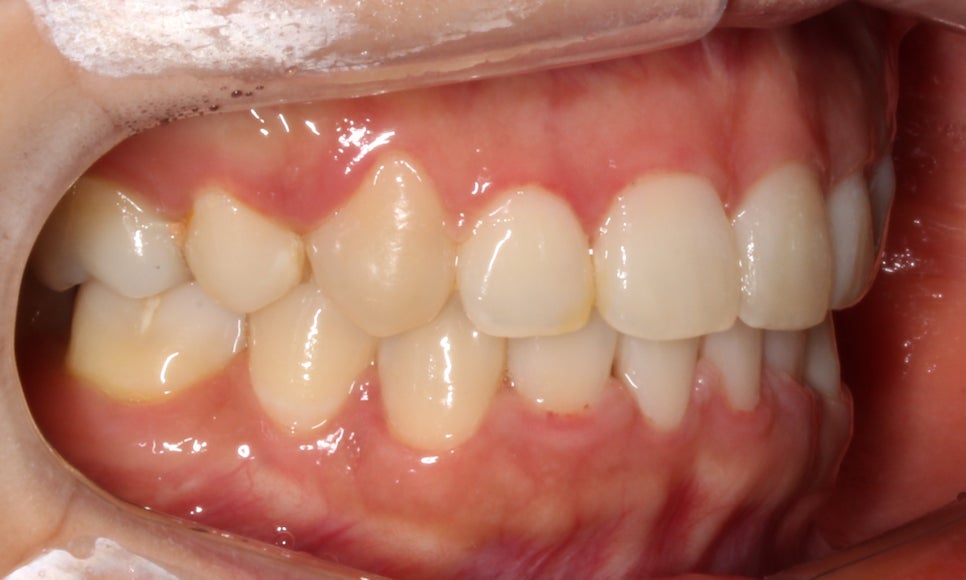

<14개월 교정이 끝난 후 모습>

교정이 끝난 모습입니다:-D

총갱이 심했던 하악도 자연스럽게

교정이 잘 마쳐졌습니다.